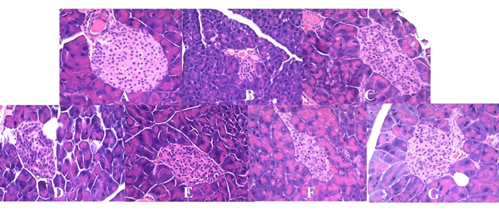

图2 不同剂量GABA酸奶对胰腺形态的影响